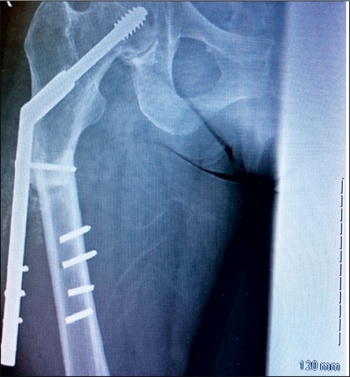

She was taken to theatre again and the DHS implant was removed. A long cephalomedullary nail was inserted. After that she was again started on physiotherapy.

The patient is being followed up in outpatients on a regular basis with check x-rays. She is now walking with a walking frame and is also on teriparatide injections.